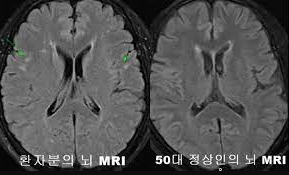

뇌의 인지기능 장애로 일상 생활을 스스로 유지하지 못하며는 '퇴행성 뇌질환' 또는 뇌혈관계 질환 이다.

그로 인해 기억력, 언어능력, 지남력(현재 자신이 놓여있는 상황) 판단력, 및 수행능력 등 기능이 저하되며 일상생활에 지장을 초래 하는 '후천적 다발성' 장애 이며, 일상생활을 제대로 수행을 못하는 임상증후군을 말한다.